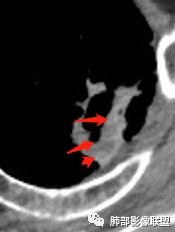

4.可疑胸膜侵犯(栽赃)。

3.内壁凹凸不平。换个视角说,有壁结节,外缘呈分叶状。

6.胸膜受侵,胸膜外脂肪密度增高;外缘膨隆为主。